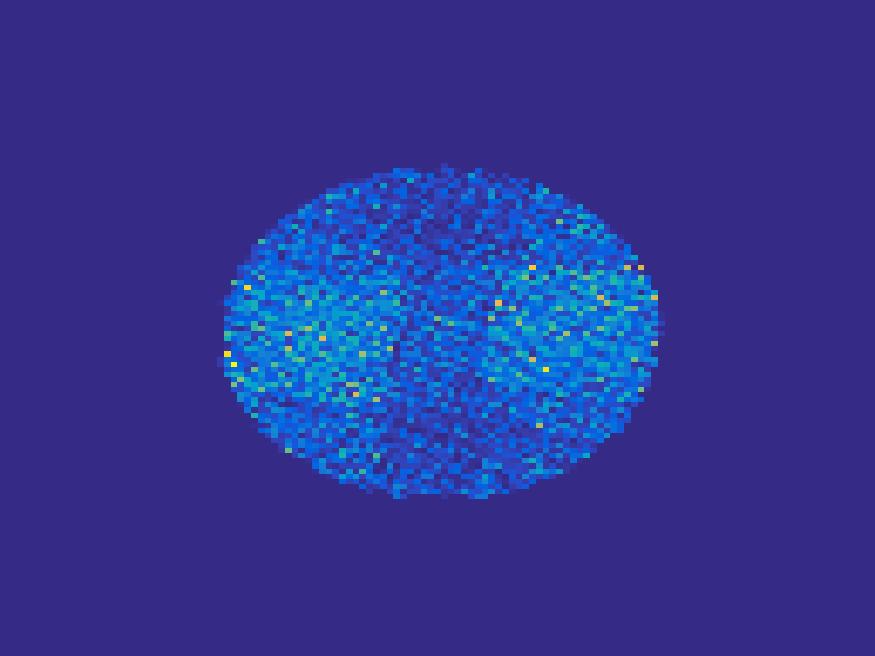

The second numerical experiment is performed on a synthetic image simulating rat’s abdomen, where the bright region represents the heart of a rat. We use the TAC in Figure 2 to simulate the dynamic images.

For the simulated images of rat’s abdomen, the same procedure is applied to generate projection data. Also, noise was added to the sinogram. Figure 5 compares the frames reconstructed by different methods. Clearly, the traditional FBP method and least square method cannot reconstruct the dynamic images with very few projections, however the proposed method reconstructs the images quite accurately. Figure 6 illustrates the comparison of the true TACs and those reconstructed by the proposed method. We can see that they are quite accurate and present small errors.